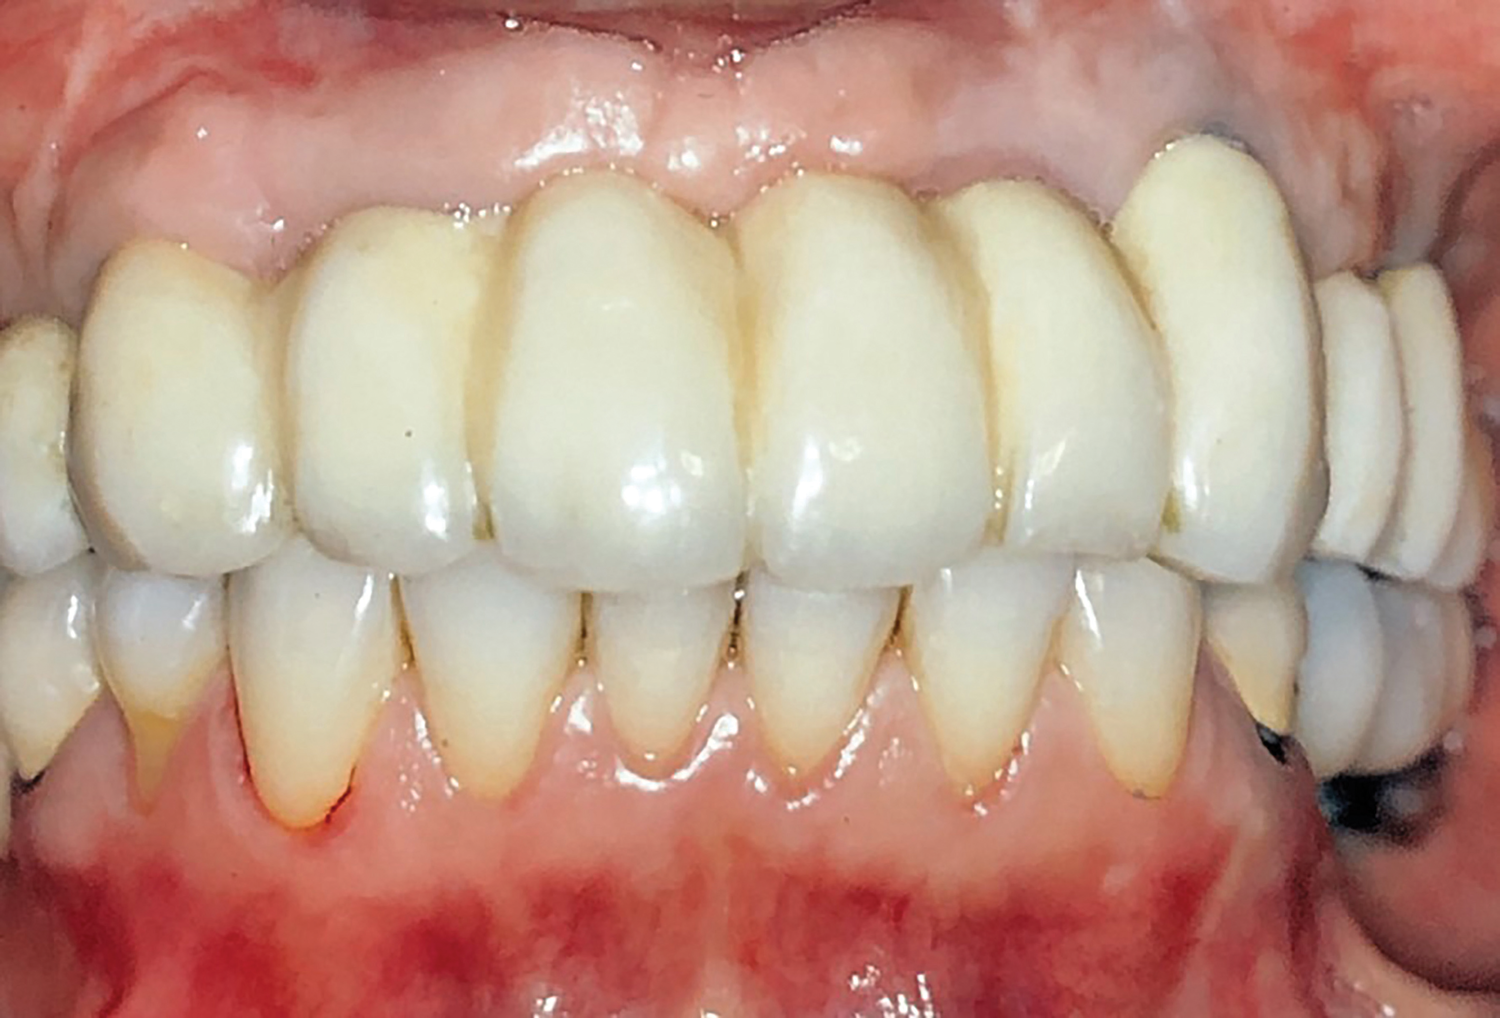

Fig 20. Frontal view at 20-year follow-up.

Figure 20

In 2020, the patient presented to the NYUCD Periodontology and Implant Dentistry Clinic. A clinical examination and radiographic evaluation showed that the patient's maxillary arch still exhibited good peri-implant soft-tissue health and stable marginal bone level with slight bone loss on implants Nos. 2, 6, 8, and 11 (Figure 18 through Figure 20). The maxillary prosthesis showed adequate stability with a slight chipped suprastructure on the porcelain on the right side. The patient was advised to substitute the implant-supported, screw-retained hybrid acrylic complete denture in the maxilla with a fixed, implant-supported, screw-retained prosthesis, which she declined due to financial considerations.

The implant-supported, screw-retained, hybrid acrylic complete denture in the maxilla and the mandibular implant fixed prostheses were delivered after torquing the custom abutments to 32 Ncm and the octa abutments to 35 Ncm, and metal frames, including the interlocks, were tried-in. After consensus was obtained on the phonetics, occlusion, and esthetics (Figure 15), the fit was verified by periapical radiographs. The patient, who was very satisfied with the result, was instructed in proper oral hygiene.